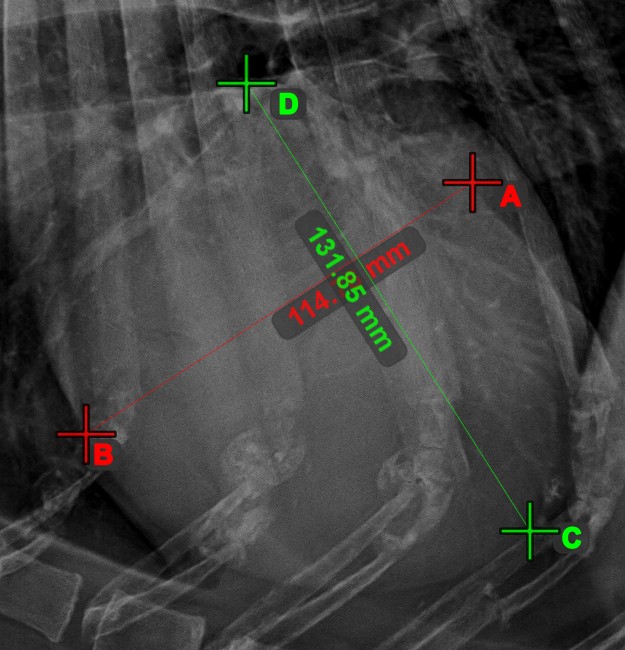

Line Intersection¶

Quickly and accurately locate and mark the intersection point between two existing lines by using the Line Intersection tool.

Select the tool from the left toolbar and assign it to one of the available mouse buttons. Select two lines that have already been drawn on the scene to complete the measurement. The intersection point of the line will be automatically calculated and marked on the scene. The intersection point of two lines will always be marked with the letter X.

Information

If two lines do not intersect directly, the intersection point of their extended projections on the scene will be marked.